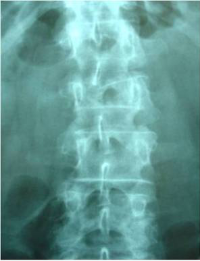

Percutaneous stabilization of unstable vertebral fractures

In cases of complex (unstable, burst, etc.) vertebral fractures, additional stabilization of the fracture by percutaneous stabilization is usually required. In cases where there also is a neurological deficit (muscle weakness, tingling in legs or arms, etc.), a decompression of the spinal canal is additionally required. A percutaneous stabilization of the spine with screws and rods discharges the load on the unstable fracture, stabilizing the whole spine and relieving pain. Depending on the patient’s bone quality, the stabilized vertebrae may be additionally cemented by kyphoplasty.